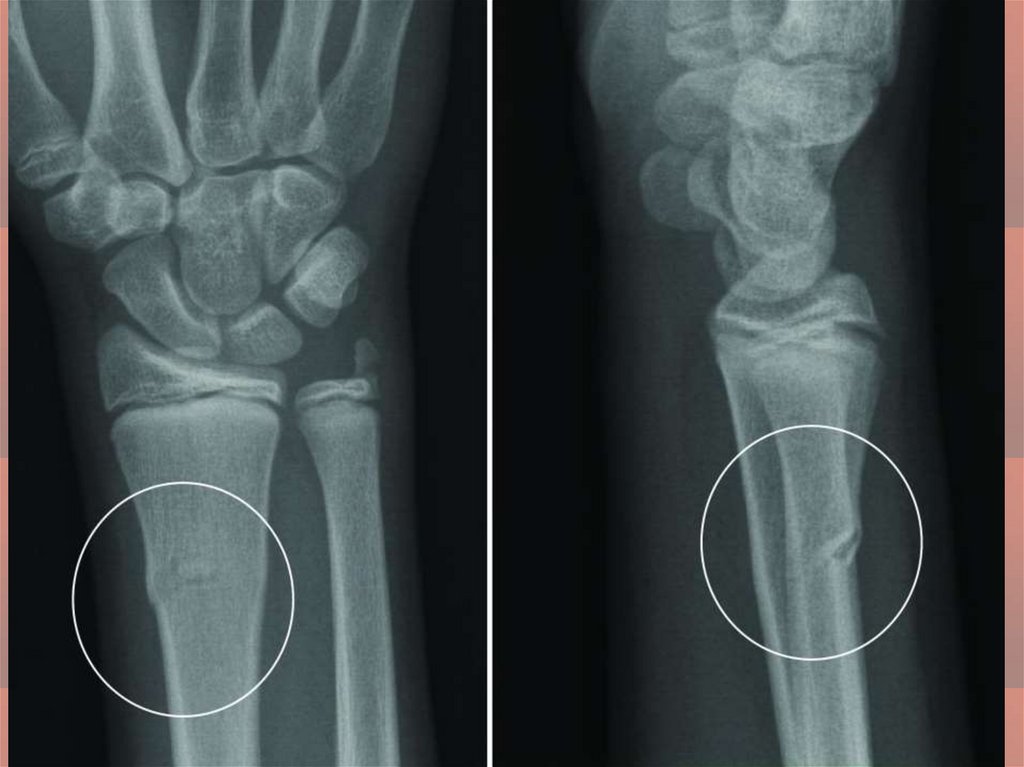

medicine

Первая помощь при травмах. Переломы